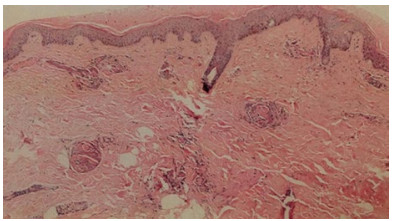

入院后予液体复苏、厄他培南1.0 g/d静脉滴注抗感染、低分子肝素6 000 U/d皮下注射抗凝治疗。查尿常规、病毒核酸五项、胸腹盆腔CT、心脏超声等检查未见明确感染灶,考虑皮肤坏死继发感染不除外。入院第2日将抗生素调整为头孢美唑2.0 g/12 h静脉滴注抗感染治疗。完善相关检查及皮肤病理。患者入院后出现黄疸加重、浓茶色尿、血小板进行性减低、肝脾肿大及腹水,其他化验检查结果:抗凝血酶Ⅲ(AT-Ⅲ)减低,网织红细胞百分比升高、骨髓增生活跃;肝素诱导的血小板减少症(HIT)抗体、活化蛋白C抵抗(APC-R)、抗心磷脂抗体(ACL)、抗β2糖蛋白1(B2GP1)、狼疮抗凝物(LA)、血清免疫固定电泳(IgA+G+M)、血清蛋白电泳均阴性。治疗上予输注血小板,新鲜冰冻血浆改善凝血功能,多烯磷脂酰胆碱、丁二磺酸腺苷蛋氨酸保肝,泼尼松30 mg/d口服控制溶血,补充白蛋白及利尿纠正低蛋白血症、减轻腹水等治疗,患者症状明显好转,血小板维持在50×109/L以上,凝血功能逐渐好转,转氨酶降至正常、胆红素水平逐渐下降,血白蛋白逐渐升高、腹水明显减少。CD55(衰变加速因子)/CD59(反应性溶血膜抑制物)结果回报明显低于正常,将低分子肝素调整为6 000 U/12 h皮下注射加强抗凝治疗。皮肤创面分泌物培养、血培养、腹水培养结果均阴性,继续头孢美唑抗感染治疗,入院第13天患者血常规正常,头面、颈部皮损范围较前缩小。入院第15天皮肤病理回报(图 2),表皮轻度角化过度,棘层萎缩变薄;真皮全层大部分血管内有纤维素样血栓形成,血管周围炎症浸润不明显,符合PF诊断。入院第17天患者体温正常,生命体征平稳。入院28 d患者皮肤出血性坏死明显好转,转至血液科进一步治疗,于3月5日好转出院(图 1)。

| 图 2 本例患者左小腿坏死组织病理(HE×40) |